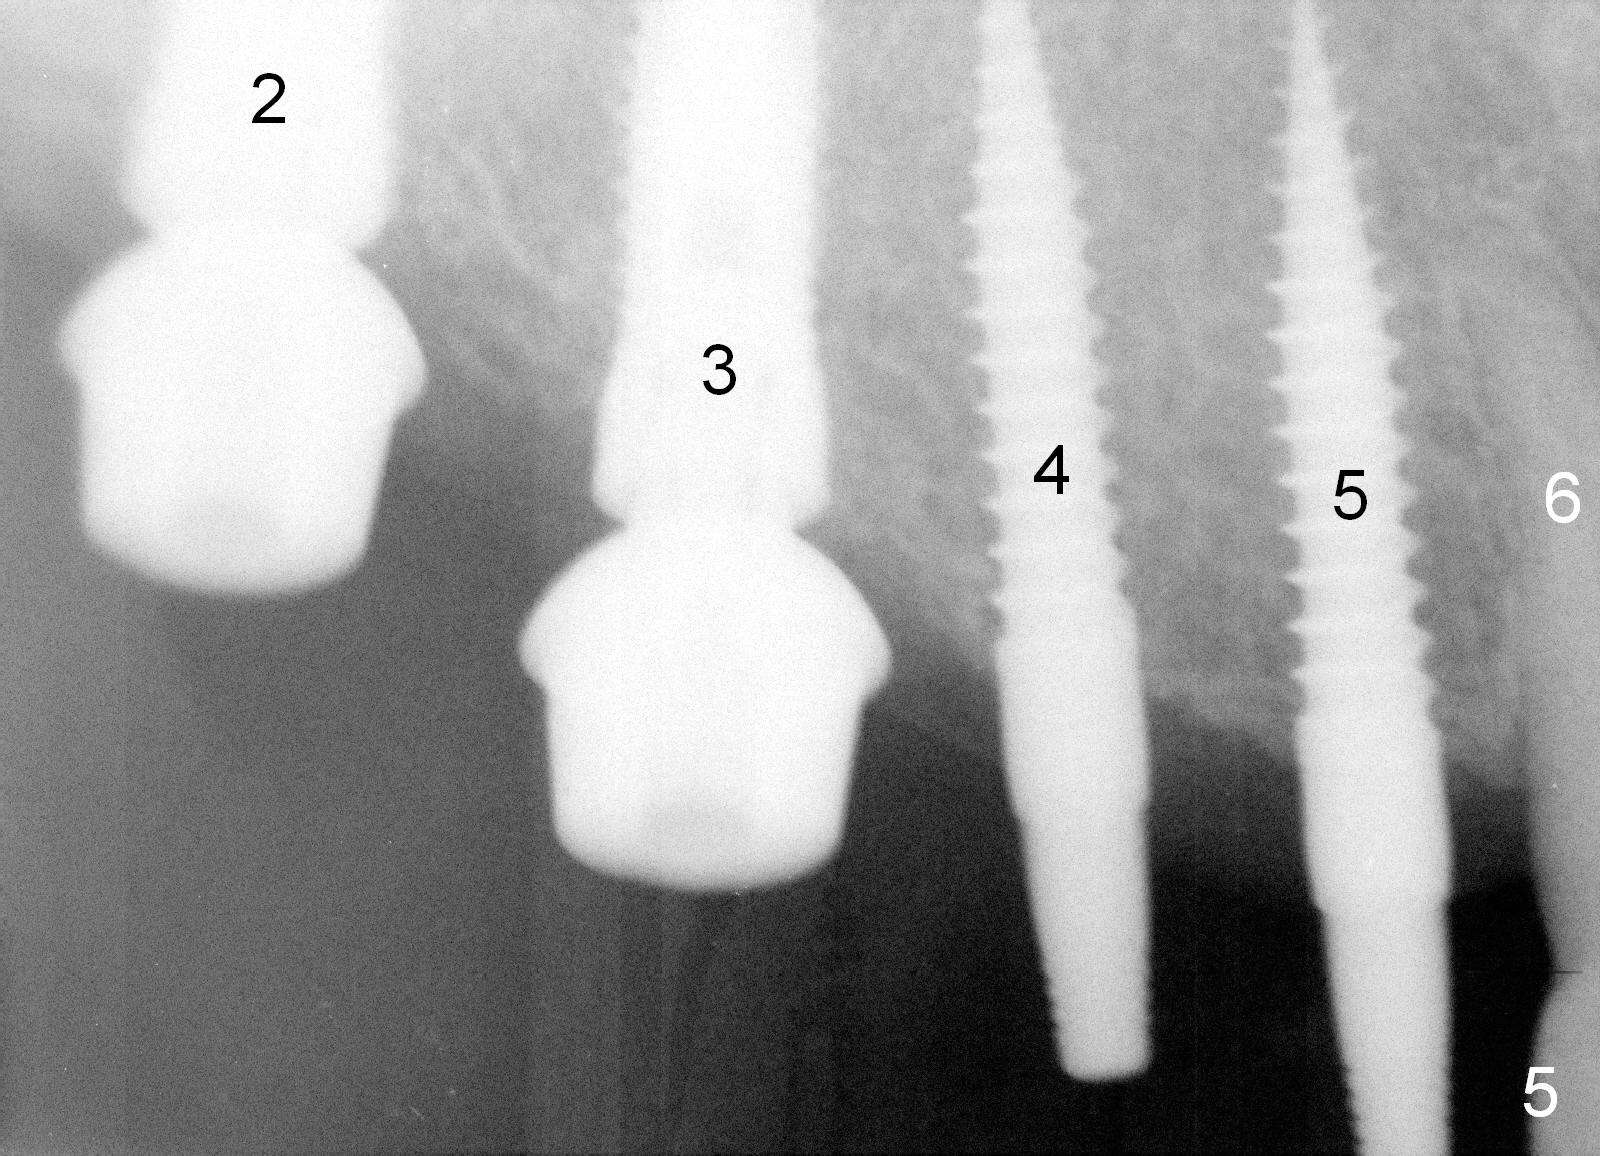

Osteotomy in the upper posteriors starts through a surgical stent for 12 mm.  After incision, each osteotomy is examined, adjusted and extended 2 mm shy of intended (Fig.1,2).  It appears that the trajectories at #4,5 are off (Fig.2).  After re-adjustment, the trajectories are acceptable (Fig.3 (red dashed line; part of the root of the tooth #6)).  Four implants are placed basically in accordance with the plan: 5.9x10 mm at #2, 5x14 at 3, and 3x14 mm 1-piece at 4 and 5 (Fig.4,5).  Fig.6 shows the narrow ridge at #4 and 5 after implant placement.  Although abutments are placed at #2 and 3, an immediate provisional bridge cannot be fabricated because of lack of enough clearance (supraeruption of the opposing dentition).